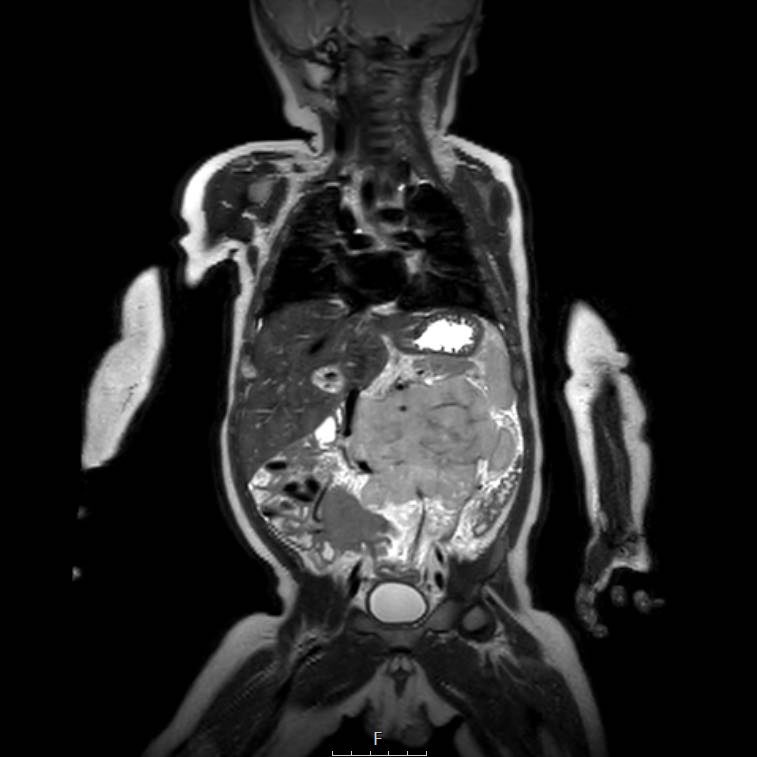

Cuộn qua chuỗi ảnh T2 theo mặt phẳng coronal.

Nghiên cứu các hình ảnh và sau đó tiếp tục đọc.

The findings are:

- Mass with encasement of the aorta and splanchnic vessels.

- Lan rộng dọc theo cột sống ngực nhưng không xâm lấn vào ống sống.

- Small liver metastases.

- Left supraclavicular mass.